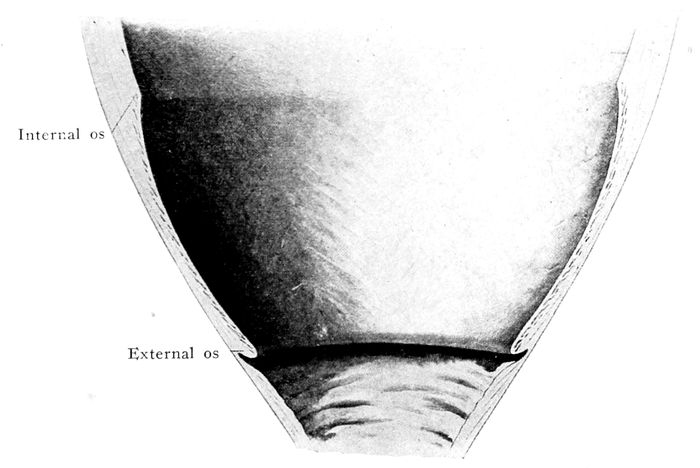

The bag of waters begins to act on the cervix |

111 |

| |

| 36. |

The effect of the pains. The cervix before labor begins |

112 |

| |

| 37. |

The effect of the pains. The cervix begins to be “effaced” |

112 |

| |

| 38. |

The effect of the pains. The cervix is effaced, and the dilatation of the os begins |

113 |

| |

| 39. |

The effect of the pains. The cervix is effaced and the os continues to dilate |

113 |

| |

| 40. |

The cervix is effaced and the os dilated |

115 |